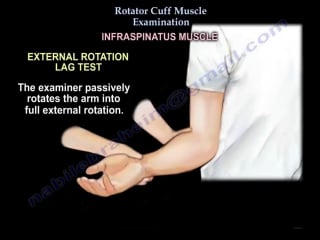

Rotator cuff muscle examination everything you need to know dr nabil ebrahe